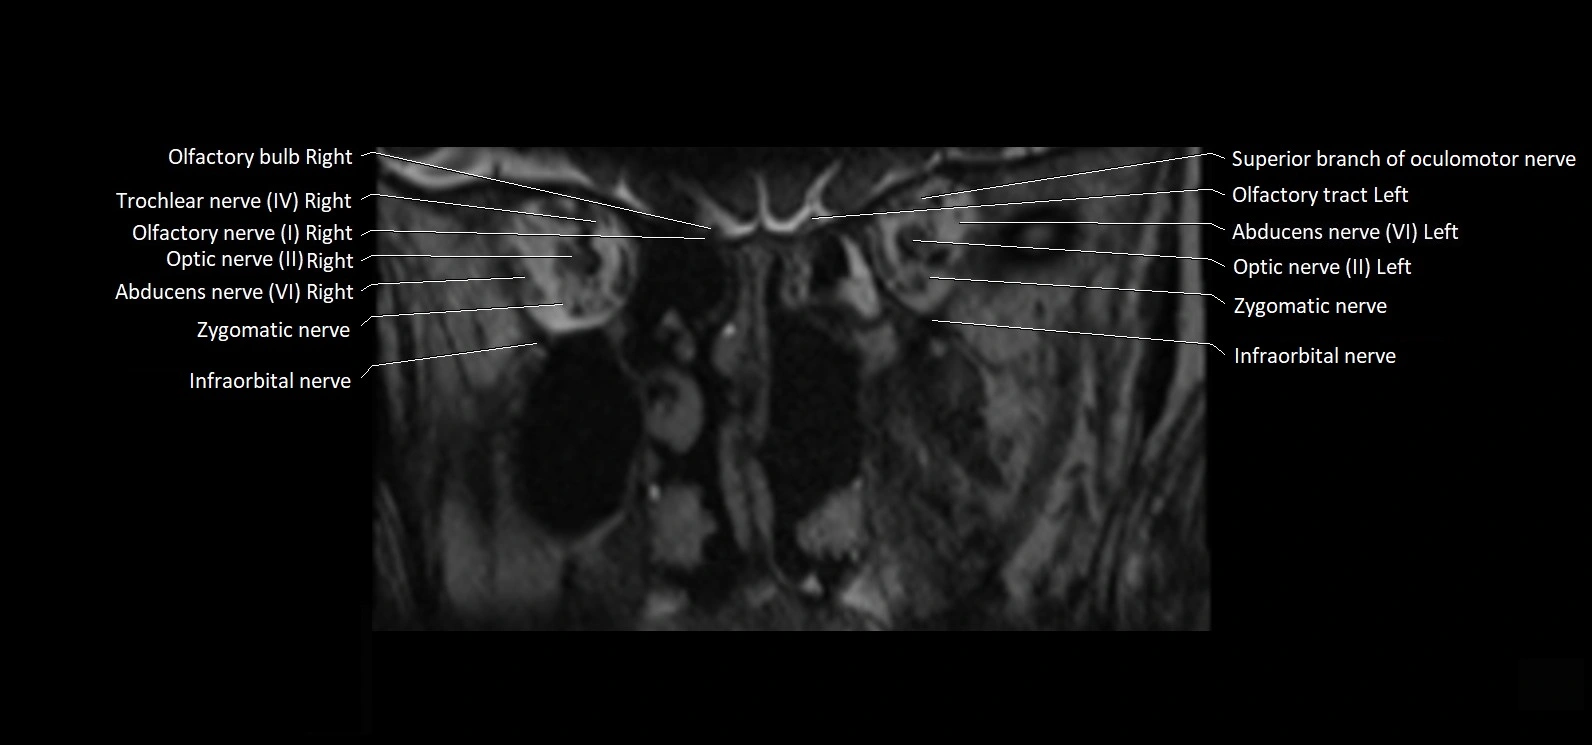

MRI Appearance

• The abducens nerve is a small, thin, linear structure

• Best visualized on high-resolution T2-weighted 3D MRI sequences (e.g., FIESTA or CISS)

• Seen as a hypointense (dark) line running from the brainstem at the pontomedullary junction, traversing the prepontine cistern, and entering Dorello’s canal under the petrosphenoidal ligament, then into the cavernous sinus, and finally the orbit

• May be challenging to visualize in standard MRI due to its small size

• Pathology may be inferred by absence, displacement, or enhancement of the nerve

MRI images

image